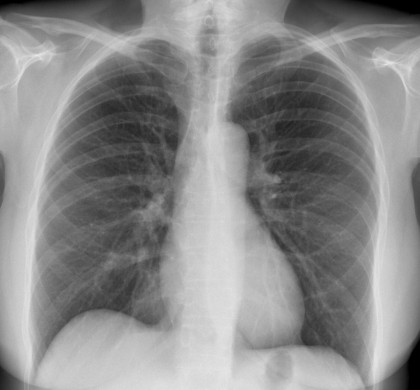

Radiografia toracică reprezintă transpunerea pe film radiografic a imaginii radioscopice. Se poate efectua fără substanţă de contrast sau se poate asocia şi substanţă de contrast efectuându-se radiografii în diferite incidenţe (AP, PA, profil, oblice). Se fac radiografii toracice pentru a distinge leziunile mici şi pentru a avea documente comparative ale evoluţiei leziunilor ce dorim să le urmărim. Ca tehnică, aceste radiografii trebuie făcute la distanţă de 2 m, pentru a nu apărea leziuni mărite şi deformate (teleradiografii). Pe filmul radiografic trebuie să se vadă desenul pulmonar dat de ramificaţia vaselor pulmonare, de la hil până aproape de periferia câmpurilor pulmonare.

Radiografia toracică de rutină include în general incidențele postero-anterioară (PA sau radiografie de față) și laterală (profil). Aceasta este o parte integrantă a evaluării diagnostice a bolilor ce implică parenchimul pulmonar, pleura, peretele toracic și, într-o măsură mai mică, căile respiratorii și mediastinul.

Imaginea radiografică este negativul imaginii radioscopice, deoarece elementele opace pentru razele X apar luminoase (albe) pe radiografii în timp ce elementele transparente dau o imagine întunecată. Astfel, la nivelul toracelui, plămânii, datorită conţinutului lor aeric, reţin într-o măsură mică radiaţiile – deoarece aerul şi gazele au un coeficient de atenuare redus. Datorită densităţii lor mici, vor apărea pe radiografie ca imagini mai întunecate separate între ele de imaginea albă, radioopacă, a opacităţii mediastinale.